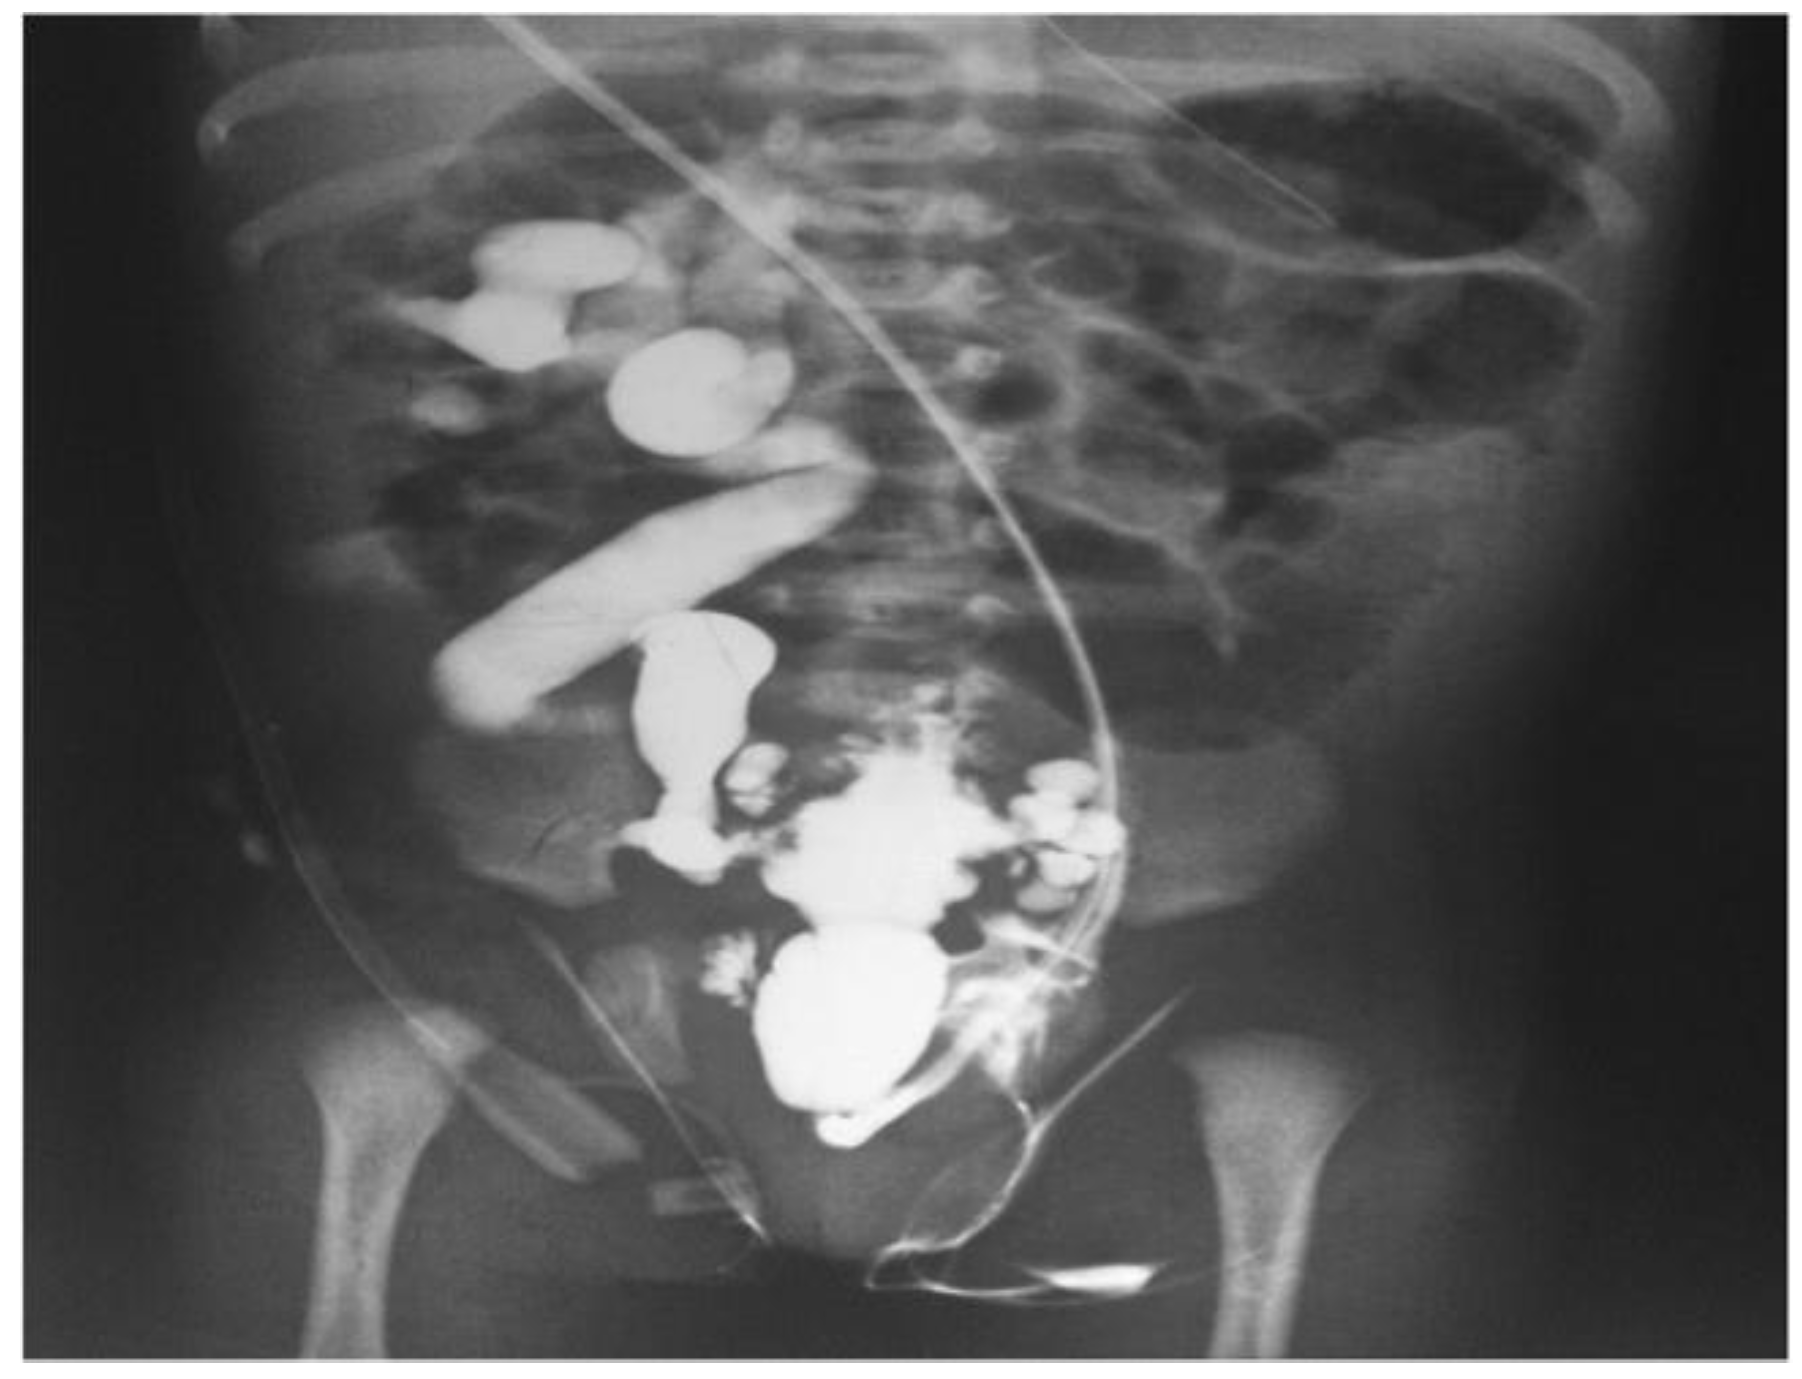

- Imaging modalities: A number of imaging modalities, such as intravenous pyelography (IVP), CT, MRI, and ultrasound, are essential for the diagnosis of juvenile kidney cancers and stones. Ultrasound is noninvasive and emits no ionizing radiation, so this method is used as a first-line imaging modality to examine renal morphology and identify structural problems (Figure 6). CT and MRI are more sensitive and specific for assessing stone load and identifying renal masses but also entail radiation exposure and require patient sedation [40].

- Improved diagnostics: AI-driven image analysis tools can enhance the identification and description of pediatric kidney cancers and tumors. Radiologists can spot minor abnormalities, characterize renal masses, and estimate tumor burden more accurately using ML algorithms that have been trained on large datasets of pediatric renal images (Figure 7). AI algorithms enable the early identification of kidney cancers and tumors by methods including pattern recognition, masking, segmentation, and quantitative analysis, allowing for confident diagnosis and timely treatment [24].